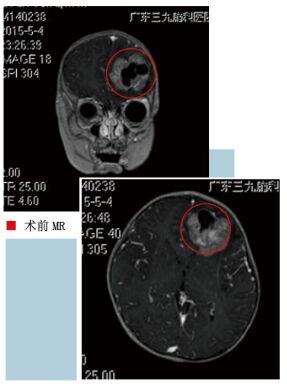

2015年4月20日患者突发神志不清,双眼上翻,四肢抽动。约3分钟后意识恢复清醒。到当地医院复查头部MRI及头部CT提示原来左额的病变体积较前明显增大。为进一步诊治家属带患儿来到了我科。入院时查体:生命体征平稳。发育正常,营养中等。神清。语言流利。双侧瞳孔=2.5mm,光反应灵敏。颈无抵抗。心肺腹(-)。四肢肌力V级,轻瘫试验-,共济失调-,各肢肌张力正常。生理反射存在,病理征未引出。入院后查MRI增强见左侧额叶占位病变,考虑肿瘤性病变,以胚胎性肿瘤可能性大(PNET可能)。经科室讨论,患儿颅内已有较大病灶,肿瘤可能性大,合并癫痫。目前患儿精神好,虽然年幼,但手术适应症明确。完善术前准备后于2014年5月8日在全麻下行“左额占位性病变切除术”。手术过程很顺利,病变完整切除。术后患儿恢复情况良好,3天后就可下床活动。病理证实为“(左额部)间变性室管膜瘤”。

术前MR考虑胚胎性肿瘤可能性大,术后病理证实为室管膜瘤。室管膜瘤来源于室管膜细胞,有神经上皮组织室管膜细胞的部位均可发病。脑室内室管膜瘤多见于第四脑室,其次为侧脑室,第三脑室少见。脑室外室管膜瘤以幕上多见,发生在脑实质内的室管膜瘤易发生囊变,脑室内肿瘤钙化较脑室外常见。幕上室管膜瘤多发生在脑实质内,最好发部位为顶叶,其次为额、颞叶。

CT平扫呈等密度或略高密度,MRIT1呈略低或等低混杂信号, T2呈高信号。幕上脑实质内室管膜瘤囊变发生率占80%,且常为大囊。室管膜瘤钙化应与少枝胶质细胞瘤鉴别:少枝胶质细胞瘤钙化常呈弯条状,囊变非常少见,CT平扫为低密度,很少强化。

室管膜瘤儿童至老年均有发生,但以青少年多见。本例发生在脑实质内,主要考虑星形细胞瘤多见,加之囊实混合不易鉴别,但病理回报后结合文献分析本病特点完全符合室管膜瘤诊断:发病年龄轻,进程缓慢,左额叶较大占位,无瘤周水肿。以实性为主,可见囊变,明显不均匀强化。熟悉本病的发病特点以及影像学表现及鉴别诊断,密切结合临床,进一步分析脑胶质瘤的组织分型,有助于进一步提高本病的诊断。